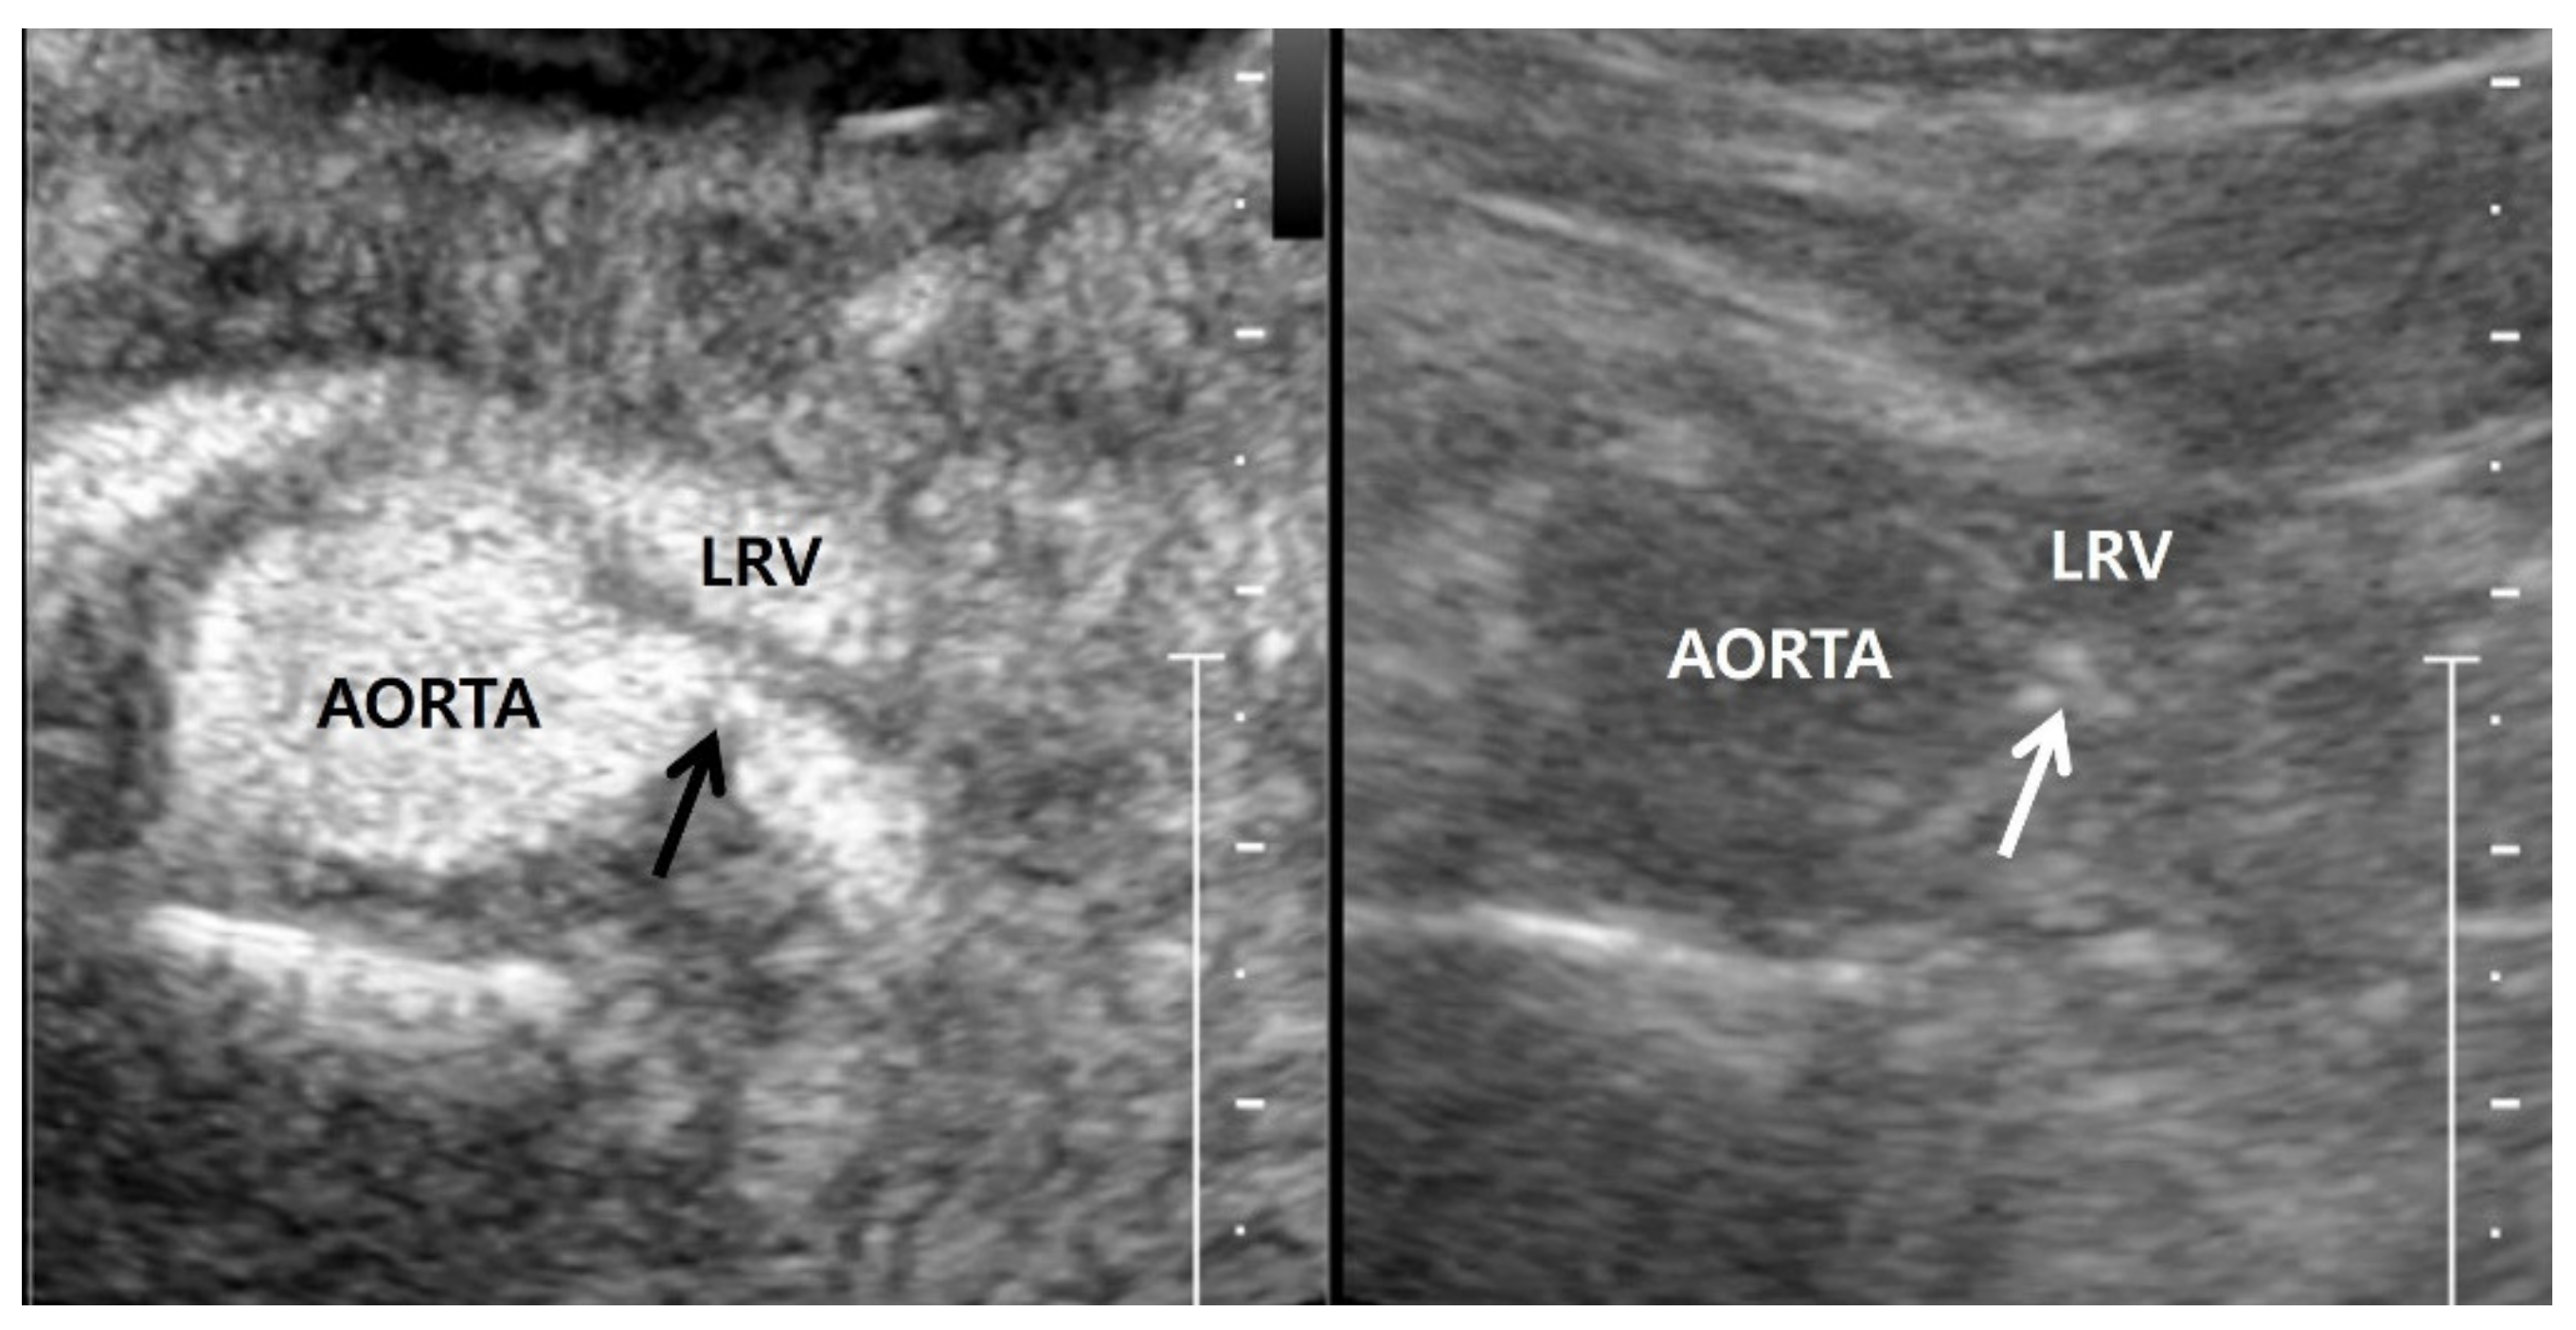

Contrast-enhanced US can be used to directly depict stenosis in the renal artery and poststenotic dilatation [23,66] (Figure 5). In addition, the US signal of an involved kidney is lower than that of the other kidney in the case of unilateral RAS [67]. The renal artery is continuously depicted when the mechanical index is low. Additionally, if a flash mode is selected during the contrast-enhanced US scan, renal artery imaging can be restarted because the in-plane US contrast material is almost all destroyed over a short period. Contrast-enhanced US can depict the renal artery only in the beginning. Renal veins and many adjacent vessels are immediately visualized following renal circulation, and, as such, may prevent precise assessment of RAS. This flash mode has the limitation where the US signal of the renal artery is weaker than that of the renal artery in the beginning of contrast-enhanced US.

Figure 5.

Contrast-enhanced US in a 60-year-old man. Contrast-enhanced US axial image (left side), which was obtained 20–30 s after Sonovue (Bracco, Milan, Italy) was intravenously injected, shows a focal stenosis in the proximal left renal artery. Gray-scale US axial image (right side), which corresponds to the contrast-enhanced US axial image, shows calcifications (white arrow) in the stenotic wall of the proximal left renal artery. LRV, left renal vein.